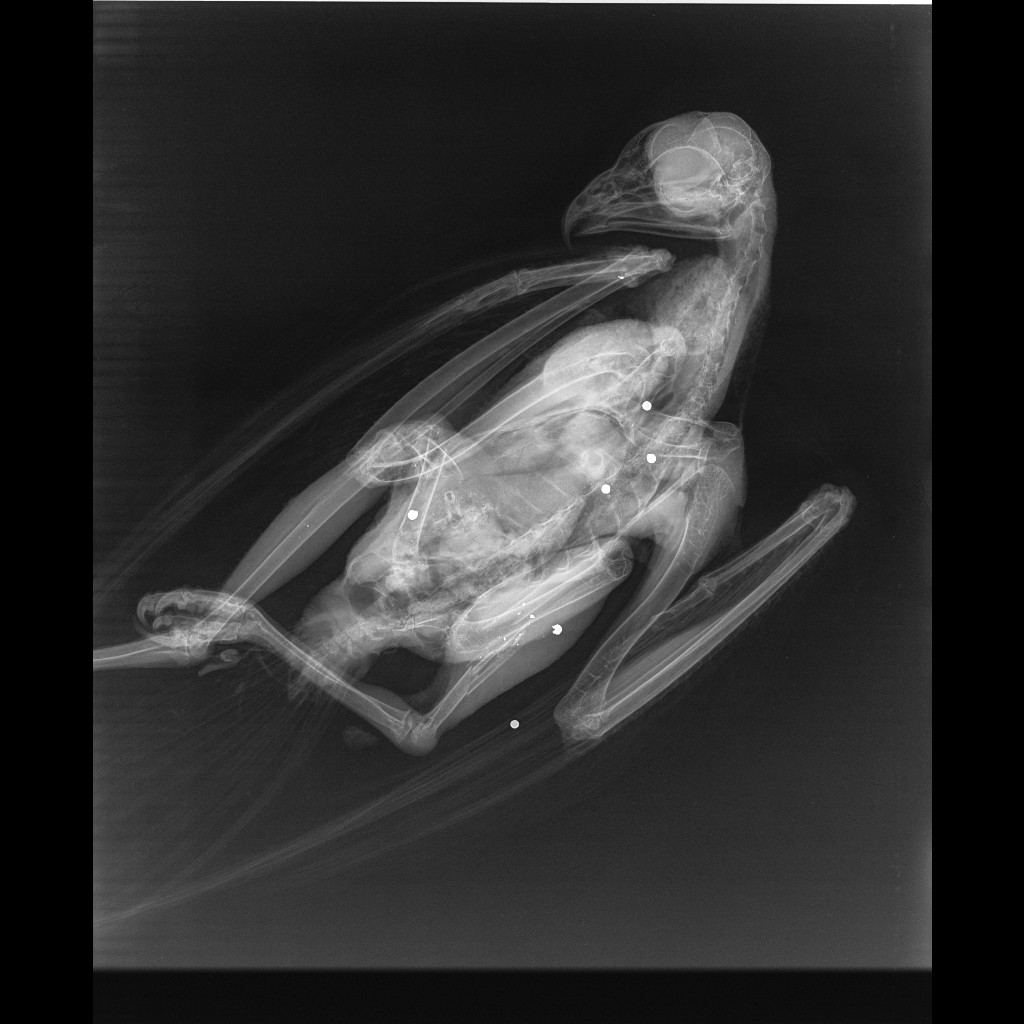

X-ray showing at least 3 shotgun pellets (highlighted by RPUK). Photo: Essex Police Wildlife Team & Colchester Owl Rescue